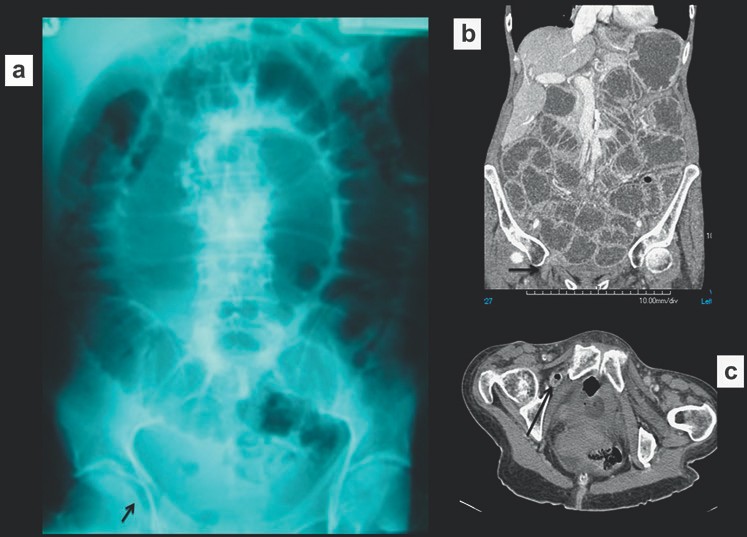

Nguyên nhân dẫn tới tắc ruột non, đặc biệt là thoát vị, đôi khi có thể nhận ra trên phim X quang và nên được tìm kiếm một các hệ thống trong tắc ruột. Điều này yêu cầu phim X quang bụng phải bao phủ cả vùng bẹn vì đó là vị trí hay thoát vị gây tắc ruột nhất. Thoát vị bịt hoặc thoát vị rốn đôi khi tạo nên các mẫu hình khí gợi ý trên phim X quang, do đó chụp cắt lớp vi tính kéo xuống mức thấp hơn để đánh giá chi tiết (Hình 2). Tắc ruột do sỏi mật và các khối ổ bụng gây tắc ruột đôi khi cũng có thể được phát hiện.

Hình 2. Tắc ruột non do thoát vị nghẹt lỗ bịt. (a) Nhiều quai ruột non giãn. Lưu ý có một ít khí dưới dây chằng bẹn ở lỗ bẹn phải (b,c) Chụp CT cho thấy một quai ruột ở giữa cơ bịt trong và cơ bịt ngoài, xác định thoát vị bịt bên phải gây tắc ruột.